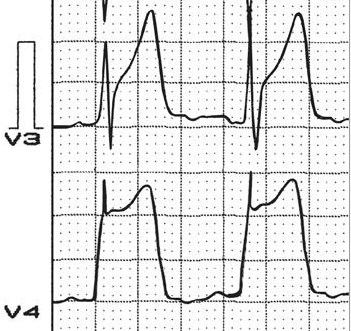

Изменения данных ЭКГ, характерных для этого заболевания, возникают лишь в момент приступа и восстанавливаются по мере утихания боли. Поэтому для постановки диагноза применяют методы коронографии и велоэргонометрической пробы. Последнее следует проводить с большой осторожностью, чтобы не допустить летальной аритмии.

Диагностируется стенокардия Принцметала ЭКГ – показаниями, свидетельствующими о:

- поднятии сегмента RS-T выше изоэлектрической линии;

- появлении патологического Q-зубца;

- увеличении зубца R;

- расширении QRS-комплекса.